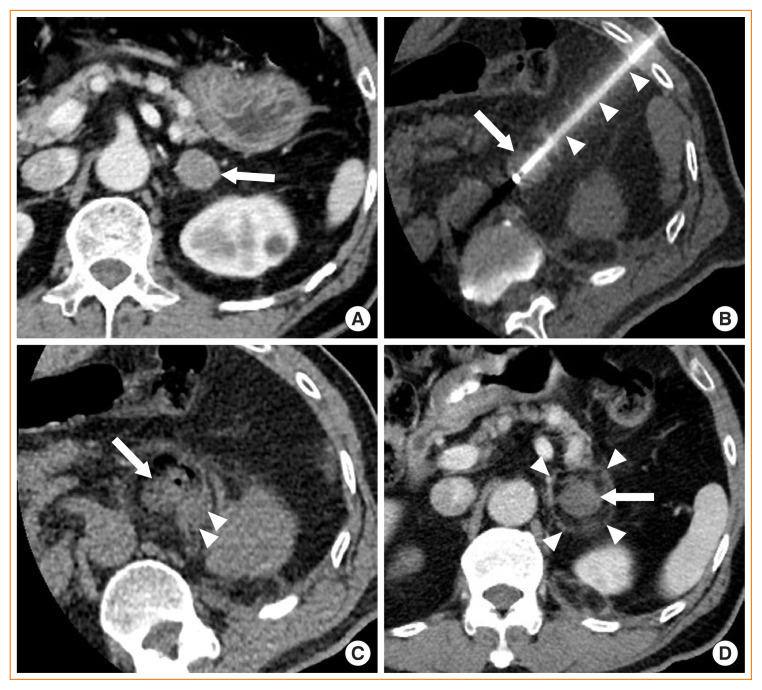

Image-guided radiofrequency ablation (RFA) has been accepted as a minimally invasive treatment for adrenal tumors in patients who are unable to undergo adrenalectomy. Accordingly, this treatment has become more readily available for treating functioning or non-functioning adrenal masses. Thus, endocrinologists need a better understanding of percutaneous RFA of adrenal tumors. The purpose of this review is to briefly describe the basic mechanism of RFA, indications and contraindications, patient preparation prior to RFA, type of complications, how to avoid complications, RFA procedures, and treatment outcomes.